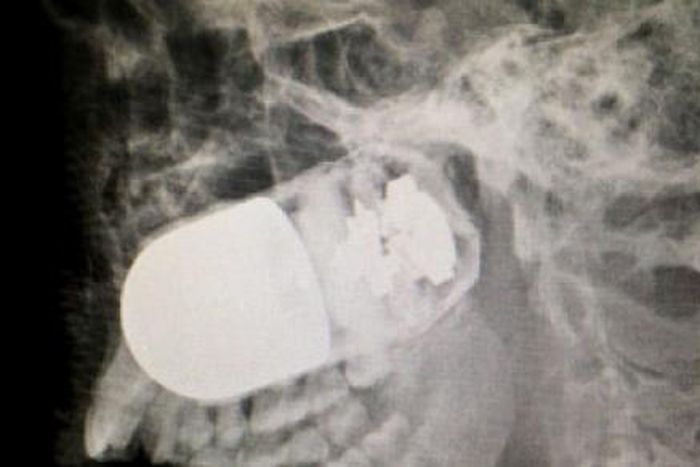

Colombian military doctors have removed a live grenade from the head of a soldier, a media report said on Friday.It said that a soldier accidentally fired a grenade launcher during a patrol in Arauca, in the eastern part of the country, leaving a grenade embedded in his comrade's head.

Transporting the victim by helicopter was too dangerous so the soldier was taken by ambulance to a military hospital in the capital Bogota. However, the journey lasted eight hours.

It said the doctors built an improvised operating theatre in the car park due to the danger of the grenade exploding.

Meanwhile Surgeon William Maldonado said that the grenade was successfully removed.

"Five minutes were decisive, if the grenade had exploded, there would have been a tragedy.

"The patient's condition has been stable since the operation on Sunday, however, up to four more operations will be needed to rebuild the soldier's face,’’ Maldonado said.